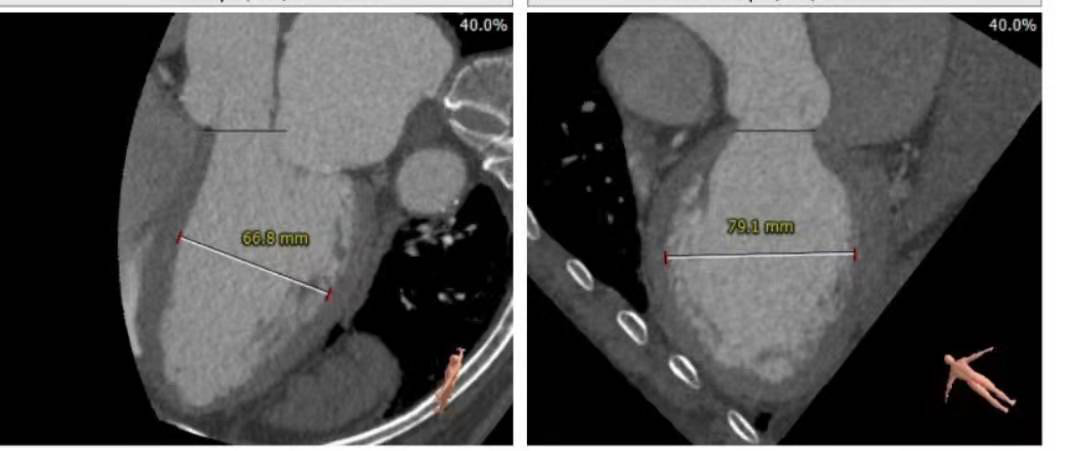

瓣环直径26.7

左室流出道直径:30.8

升主动脉增宽

冠脉高度尚可。左冠高度:13.4,右冠高度:20.6。心脏角度52

心室较大,心尖超薄